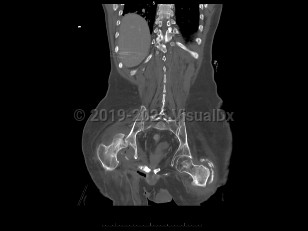

Septic arthritis

An infection of a joint most frequently caused by bacteria (although fungi, parasites, and mycobacteria may also rarely cause this infection).

This infection occurs most commonly as a result of hematogenous seeding of the joint in the setting of bacteremia. A joint may be inadvertently inoculated with a pathogen at the time of surgery or trauma. In some patients, a severe soft tissue infection may spread to involve a nearby joint.

Patients present with a swollen, warm, stiff, and painful joint. Fever may be present. The majority of the time, a single joint (usually the knee) is involved. Symptoms develop over 1-2 weeks. If the infection is caused by N gonorrhoeae, patients classically also present with a rash and tenosynovitis. If the infection is due to fungi or mycobacteria, the symptoms may be subtler and may worsen more gradually.